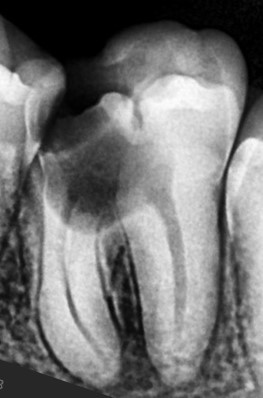

Before

After

Lower Molar

Extraction Avoided

Infected Molar Saved

Deep infection had weakened the lower molar significantly. Precision root canal treatment helped avoid extraction.

Deep infection cleaned

Tooth saved from removal

Normal chewing restored